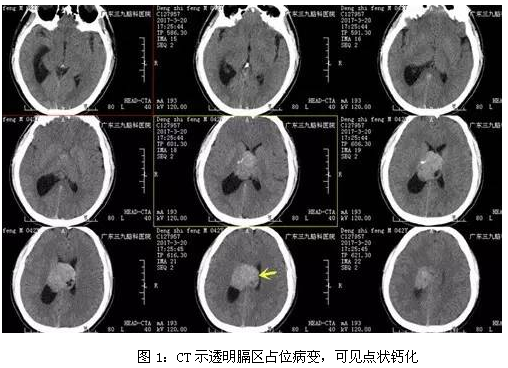

邓男子,42岁,头晕头痛伴恶心呕吐1周余入院,入院后完善相关检查,CT示透明膈区占位病变,可见点状钙化,CTA提示肿瘤其内血管丰富,磁共振检查结果提示脑室内占位性病变,瘤体大小约为5.1cm*3.9cm*4.2cm,行脑室内占位性病变切除术手术,手术由神经外一科主任张良主刀完成,过程顺利,术后磁共振提示肿瘤切除,术后恢复良好。